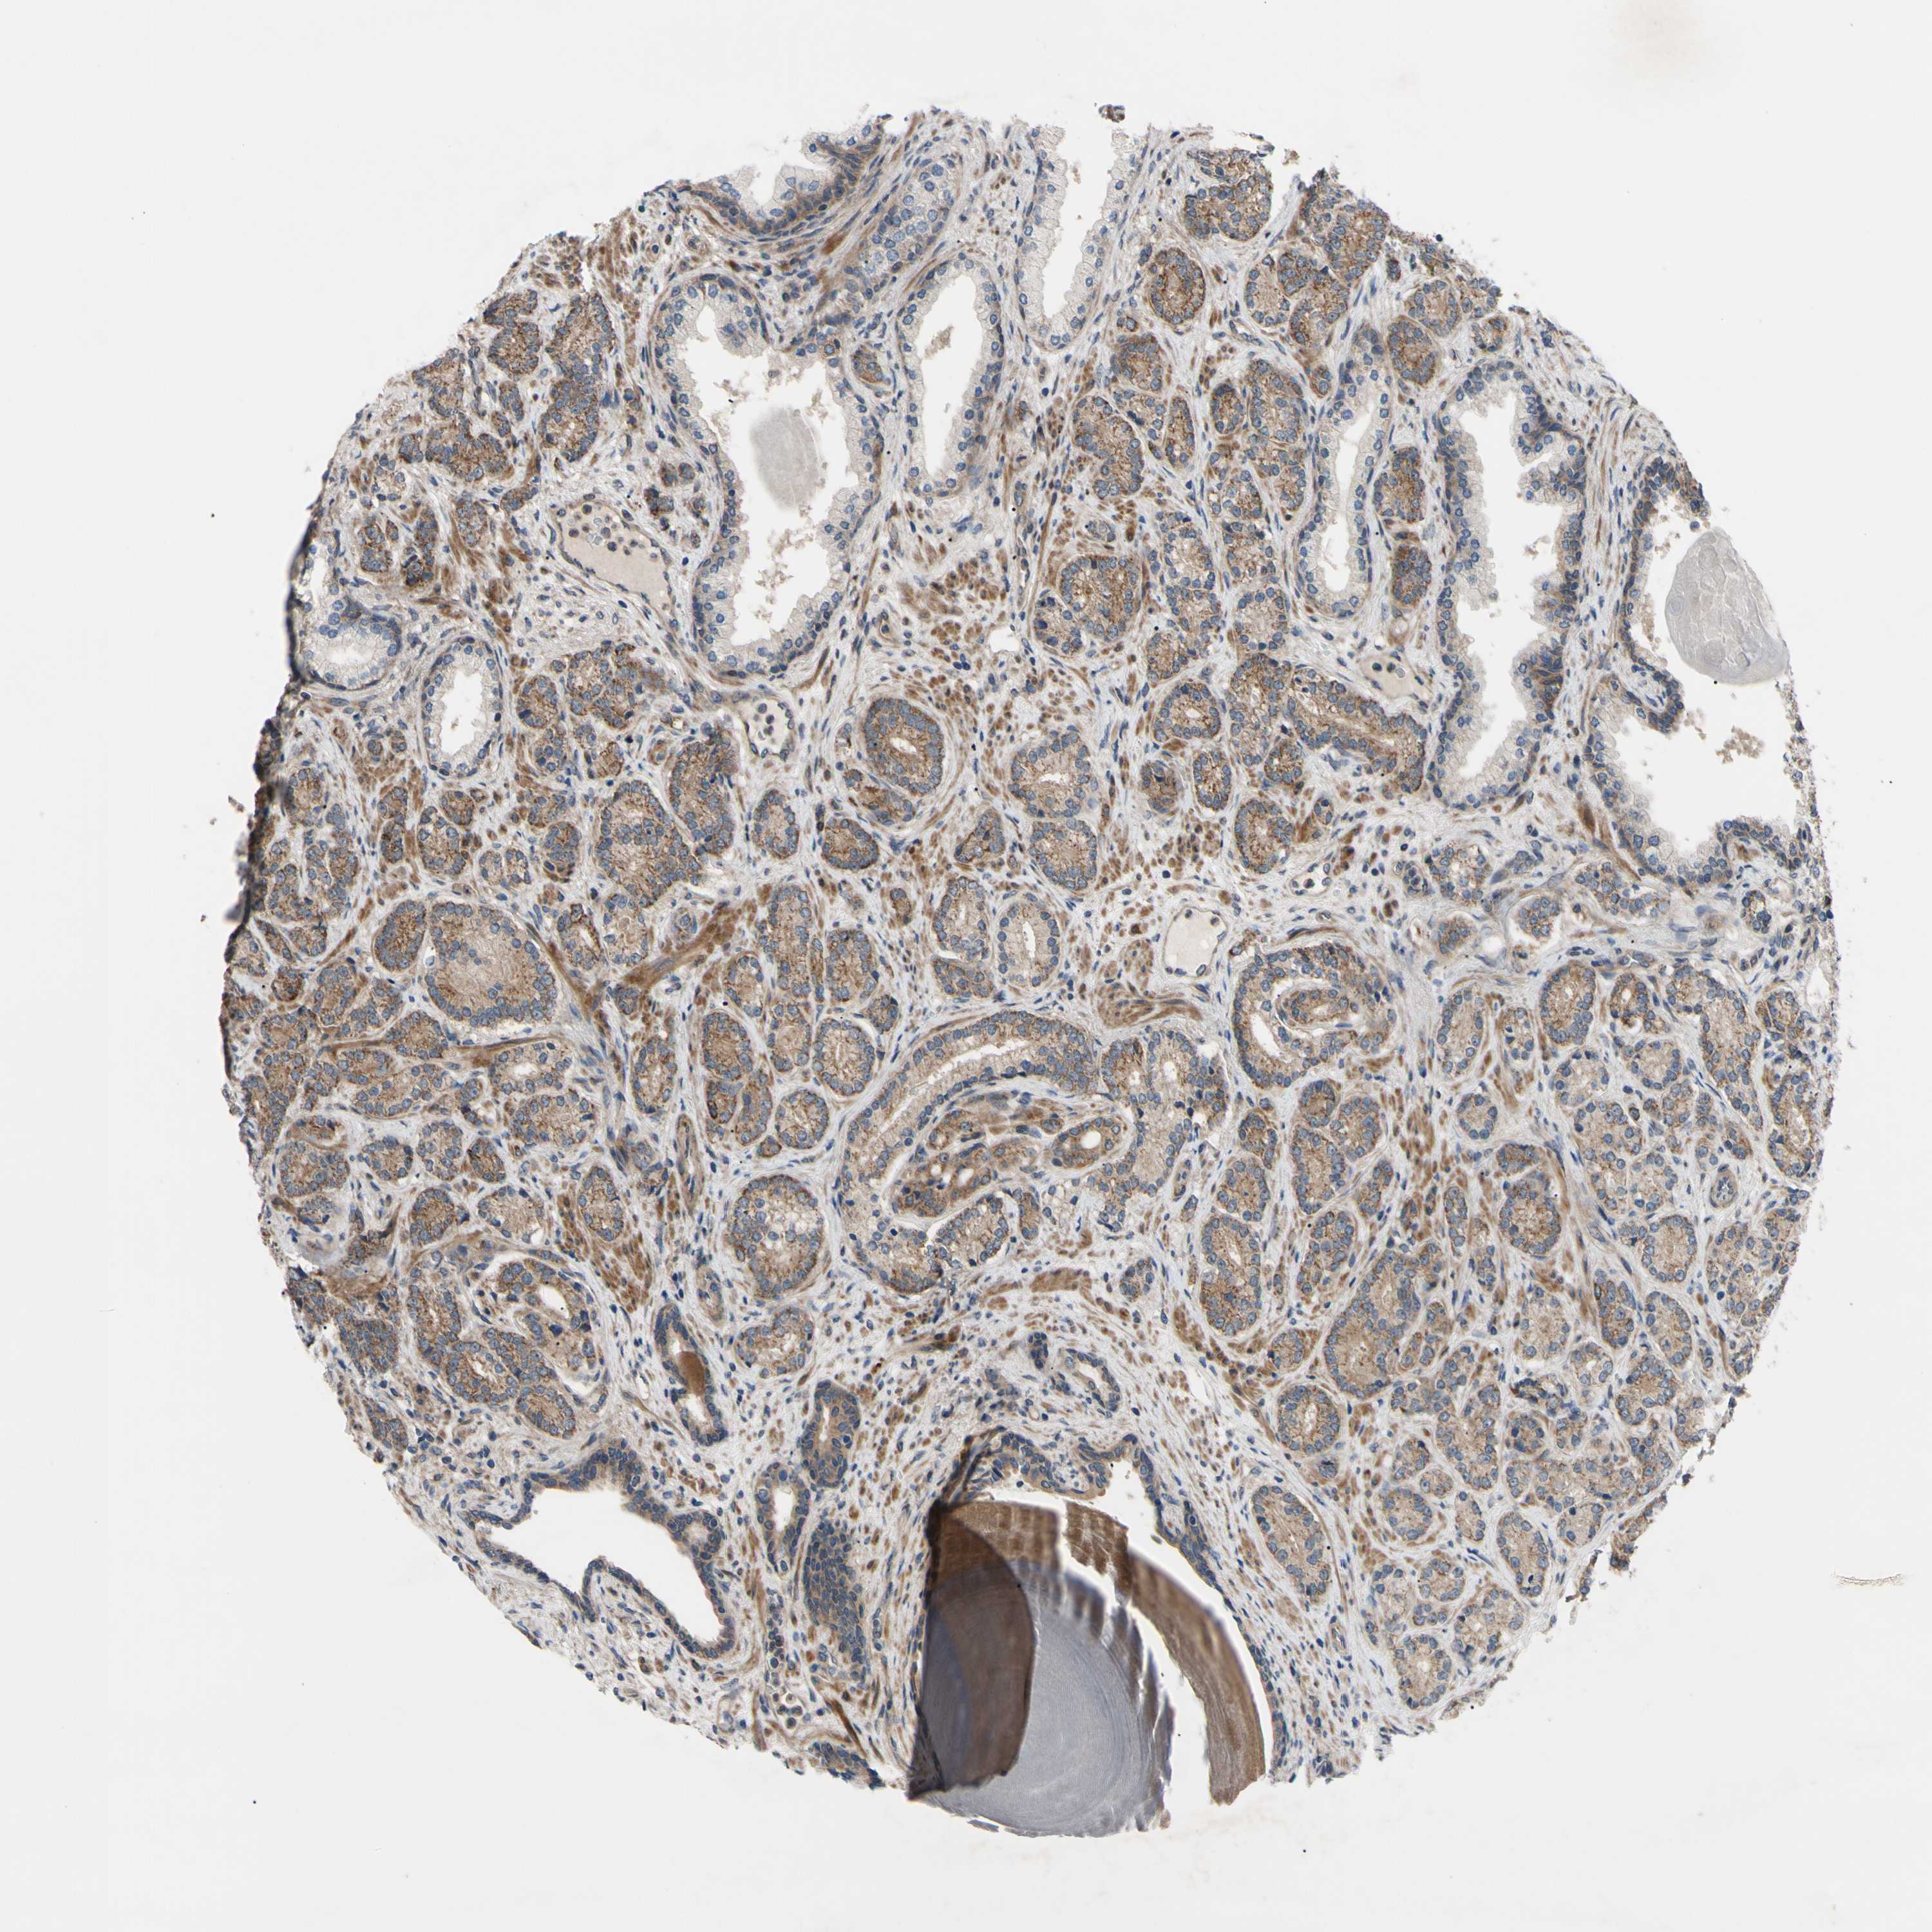

PROSTATE CANCER - Protein expressioni

A mouse-over function shows sample information and annotation data. Click on an image to view it in a full screen mode. Samples can be filtered based on level of antibody staining by selecting one or several of the following categories: high, medium, low and not detected. The assay and annotation is described here.

Note that samples used for immunohistochemistry by the Human Protein Atlas do not correspond to samples in the TCGA dataset.

Antibody stainingi

Antibody staining in the annotated cell types in the current human tissue is reported as not detected, low, medium, or high, based on conventional immunohistochemistry profiling in selected tissues. This score is based on the combination of the staining intensity and fraction of stained cells.

Each image is clickable and will lead to virtual microscopy that enables deeper exploration of all samples and also displays staining intensity scores, fraction scores and subcellular localization as well as patient and tissue information for each sample.

Antibody HPA020095

Antibody HPA020138

Antibody CAB010878

Antibody CAB080402

Staining

High

Medium

Low

Not detected

Intensity

Strong

Moderate

Weak

Negative

Quantity

>75%

75%-25%

<25%

None

Location

Nuclear

Cytoplasmic/membranous

Cytoplasmic/membranous,nuclear

Adenocarcinoma, High grade

Adenocarcinoma, Low grade

Adenocarcinoma, NOS

Adenocarcinoma, Medium grade